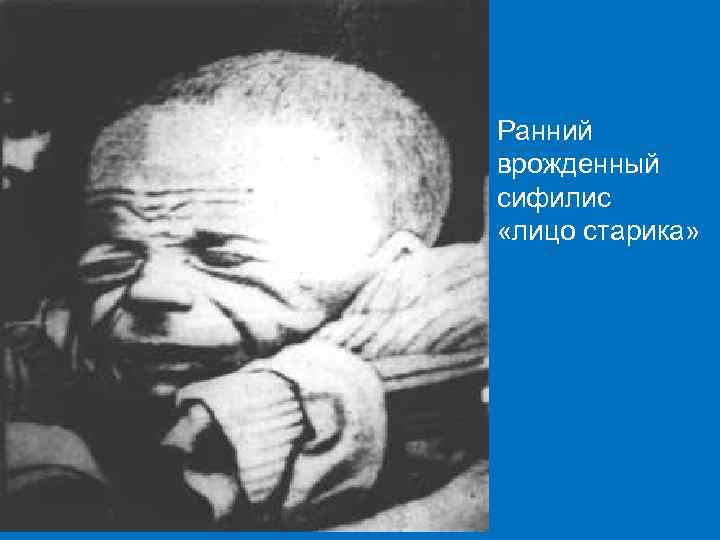

Ранний врожденный сифилис грудного возраста § Ребенок слабо развит, маленькая масса тела. § Кожа дряблая, складчатая (отсутствует подкожножировая клетчатка), «лицо старика» . § Гидроцефалия, родничок напряжён, лобные бугры выражены, череп имеет удлиненную форму, кожные вены головы расширены. § Худые синюшные конечности. § Ребёнок беспокоен, часто кричит, развивается плохо, прогрессируют вялость и дистрофии. § Присоединившиеся интеркуррентные заболевания, часто приводят к ранней гибели ребенка. § Поражение кожи и слизистых оболочек соответствуют вторичному периоду приобретенного сифилиса.

Гидроцефалия, родничок напряжен, лобные бугры выражены, череп имеет удлиненную форму, кожные вены головы расширены.